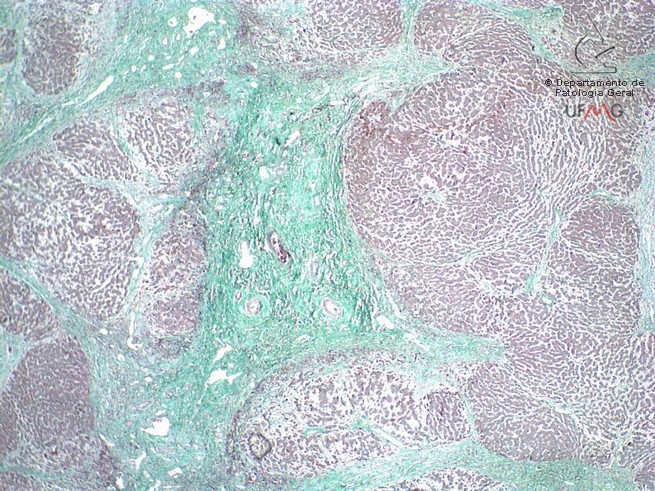

Fígado

Coloração: Tricrômico de Gomori

Cirrose hepática